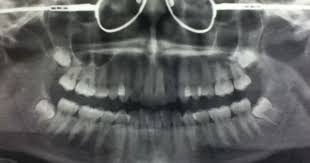

Panoramic Taken On Our Office On A 10 Year Old Child Showing Permanents As Well As Primary Teeth Unerupted Dental Treatment Dental Clinic Dental